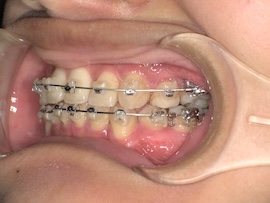

そこから1ヶ月後、

再度レントゲンにて左上親知らずの状態を確認したところ手前の歯に引っかかっていそうだったので、親知らずにもブラケットをつけてバネで押しながら引っ張るように調整してもらいました。